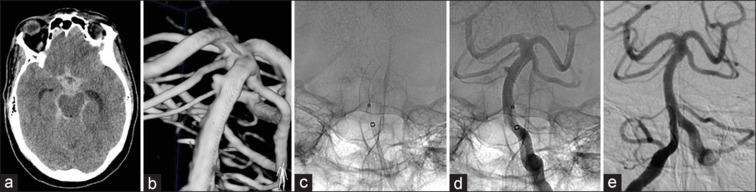

目的:当出现急性动脉瘤破裂时,神经外科医生可能会选择使用血流分流器(fd)。然而,关于其安全性和潜在的血栓栓塞和出血并发症的证据有限,它们的使用极为罕见,而且往往相当有限。在这项研究中,我们评估了使用FD支架治疗急性破裂颅内动脉瘤患者的治疗相关并发症以及临床和放射学结果。材料和方法:我们对2012年至2024年蛛网膜下腔出血后15天内接受FDs治疗的患者进行了回顾性分析。评估患者的人口统计学特征、动脉瘤特征、手术细节以及临床和影像学随访。结果:本研究纳入30例患者,平均年龄55.6岁。大多数动脉瘤位于前循环内,大小不一。形态学上,动脉瘤为囊状(43.3%)、水疱样(40%)和梭状/夹层(16.7%)。从破裂到治疗的平均时间为4.4天。所有病例均成功释放FD。治疗后再出血发生率为10%,缺血性并发症发生率为6.7%,治疗相关死亡率为6.6%,总死亡率为13.3%。出院时,70%的患者获得了良好的功能预后。平均放射学随访时间为26个月,1个月时57.1%的患者观察到完全的动脉瘤闭塞,1年后随访的患者100%(40%)观察到完全的动脉瘤闭塞。结论:尽管谨慎的患者选择和替代治疗的考虑是必要的,但对于急性破裂动脉瘤的分流治疗显示出良好的结果。未来需要前瞻性的多中心研究来验证初步发现并优化这一高危患者群体的治疗方案。

Results: The study included 30 patients with a mean age of 55.6 years. Most aneurysms were located within the anterior circulation and were either small or medium-sized. Morphologically, aneurysms were saccular (43.3%), blister-like (40%), and fusiform/dissecting (16.7%). The mean time from rupture onset to treatment was 4.4 days. FD release was successfully achieved in all cases. Posttreatment rebleeding occurred in 10% of patients, ischemic complications in 6.7%, and treatment-related mortality was 6.6%, with an overall mortality of 13.3%. At discharge, 70% of patients achieved a favorable functional outcome. The mean available radiological follow-up period was 26 months, with complete aneurysm occlusion observed in 57.1% of patients at 1 month and in 100% of those available (40%) for follow-up after 1 year.